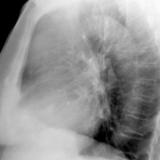

Case 8a Thymoma PA

Date: 03/27/2009

Views: 9457